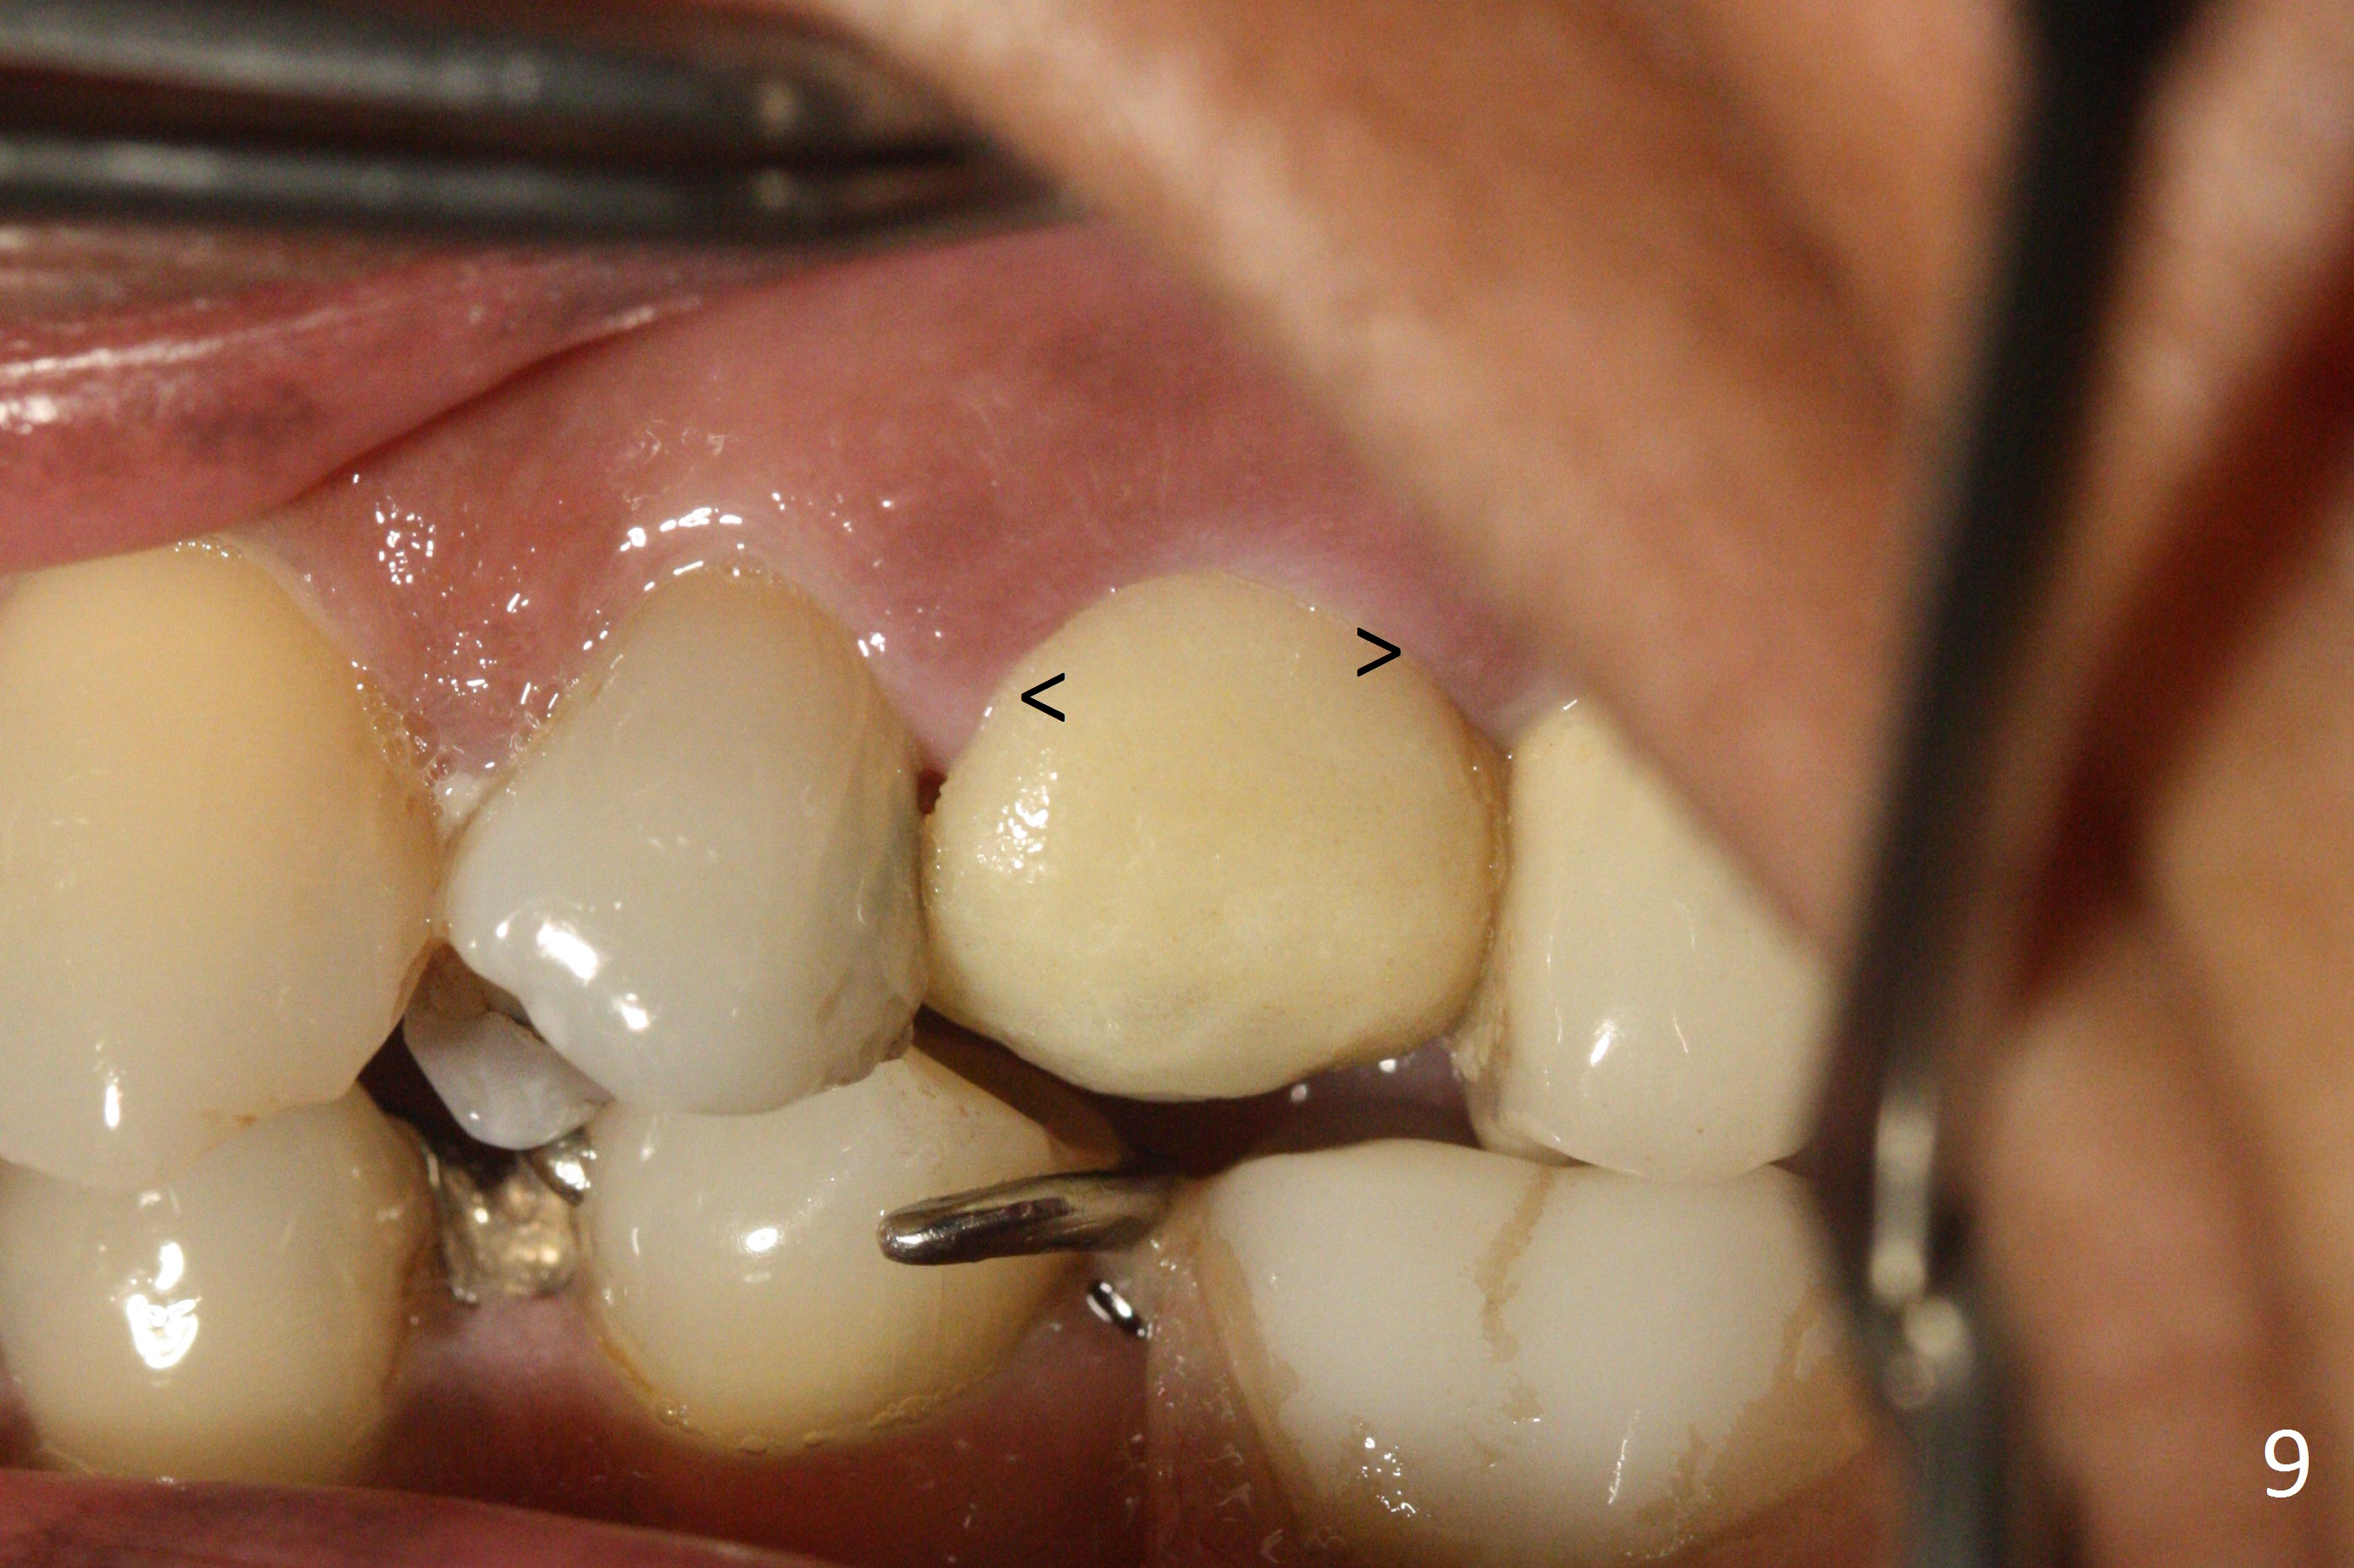

Since the apical native bone is limited at #13 after extraction, no PA is taken until a 4x11 mm dummy implant is placed after 1.6 mm and 3.3 mm drills for 13 mm (Fig.1). After using Lindamann bur to move the osteotomy distal and reusing 3.3 mm drill, the trajectory of a 4.5x11 mm IBS dummy implant improves (Fig.2,3 with low stability). When the implant is removed, the buccal portion of the socket is found to be perforated (Fig.4 P). Although the reason for the perforation is unknown, it is repaired by insertion of a piece of PRF plug, followed by allograft. #1 and 2 in Fig.4 represent the 1st and 2nd osteotomies, as shown in Fig.1 and 2, respectively. The trajectory of the final 5x13 mm implant is acceptable (Fig.5-7, different angulations), so is insertion torque (45 Ncm). After placing a 5.5x4(4) mm abutment, an immediate provisional is fabricated (Fig.8 P) with occlusal clearance (*). The interdental papillae remain in place 12 days postop (Fig.9 *). There is no sign of postop sinus infection. The provisional is loose 18 days postop; the abutment is changed to 5x4(3) mm (Fig.10). It is difficult to catch the mesial margin of the abutment for impression 4 months postop, due to poor oral hygiene and the short cuff (3 mm, Fig.11). The appointment for impression is rescheduled with emphasis on oral hygiene and no wearing the provisional for a few days prior to next appointment. Bone has grown into the space between the 1st and 2nd threads 5 months post cementation (Fig.12) and the bone is normal, solid and dense 2 years 11 months post cementation (Fig.13 >). There is mesial open margin of the tooth #14 (Fig.13,14 *).